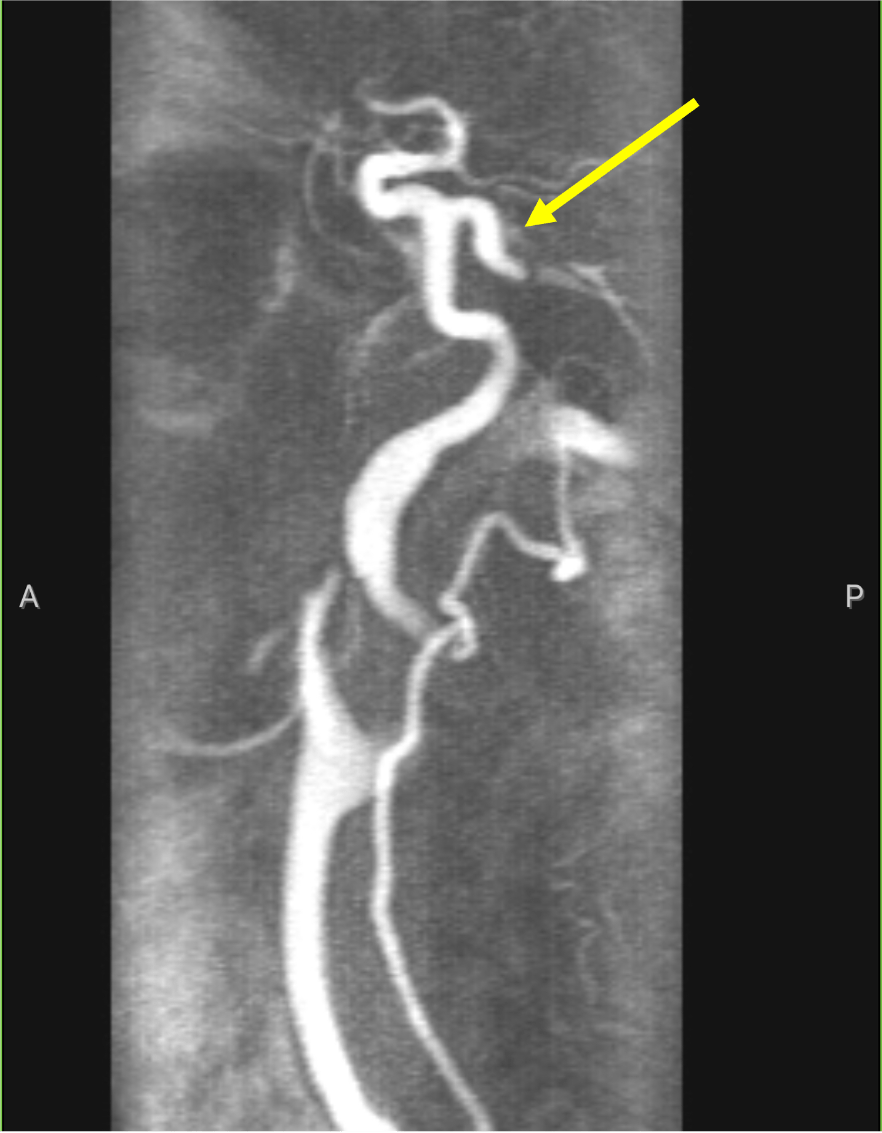

In this patient:

What is this artery:

Persistent trigeminal artery!